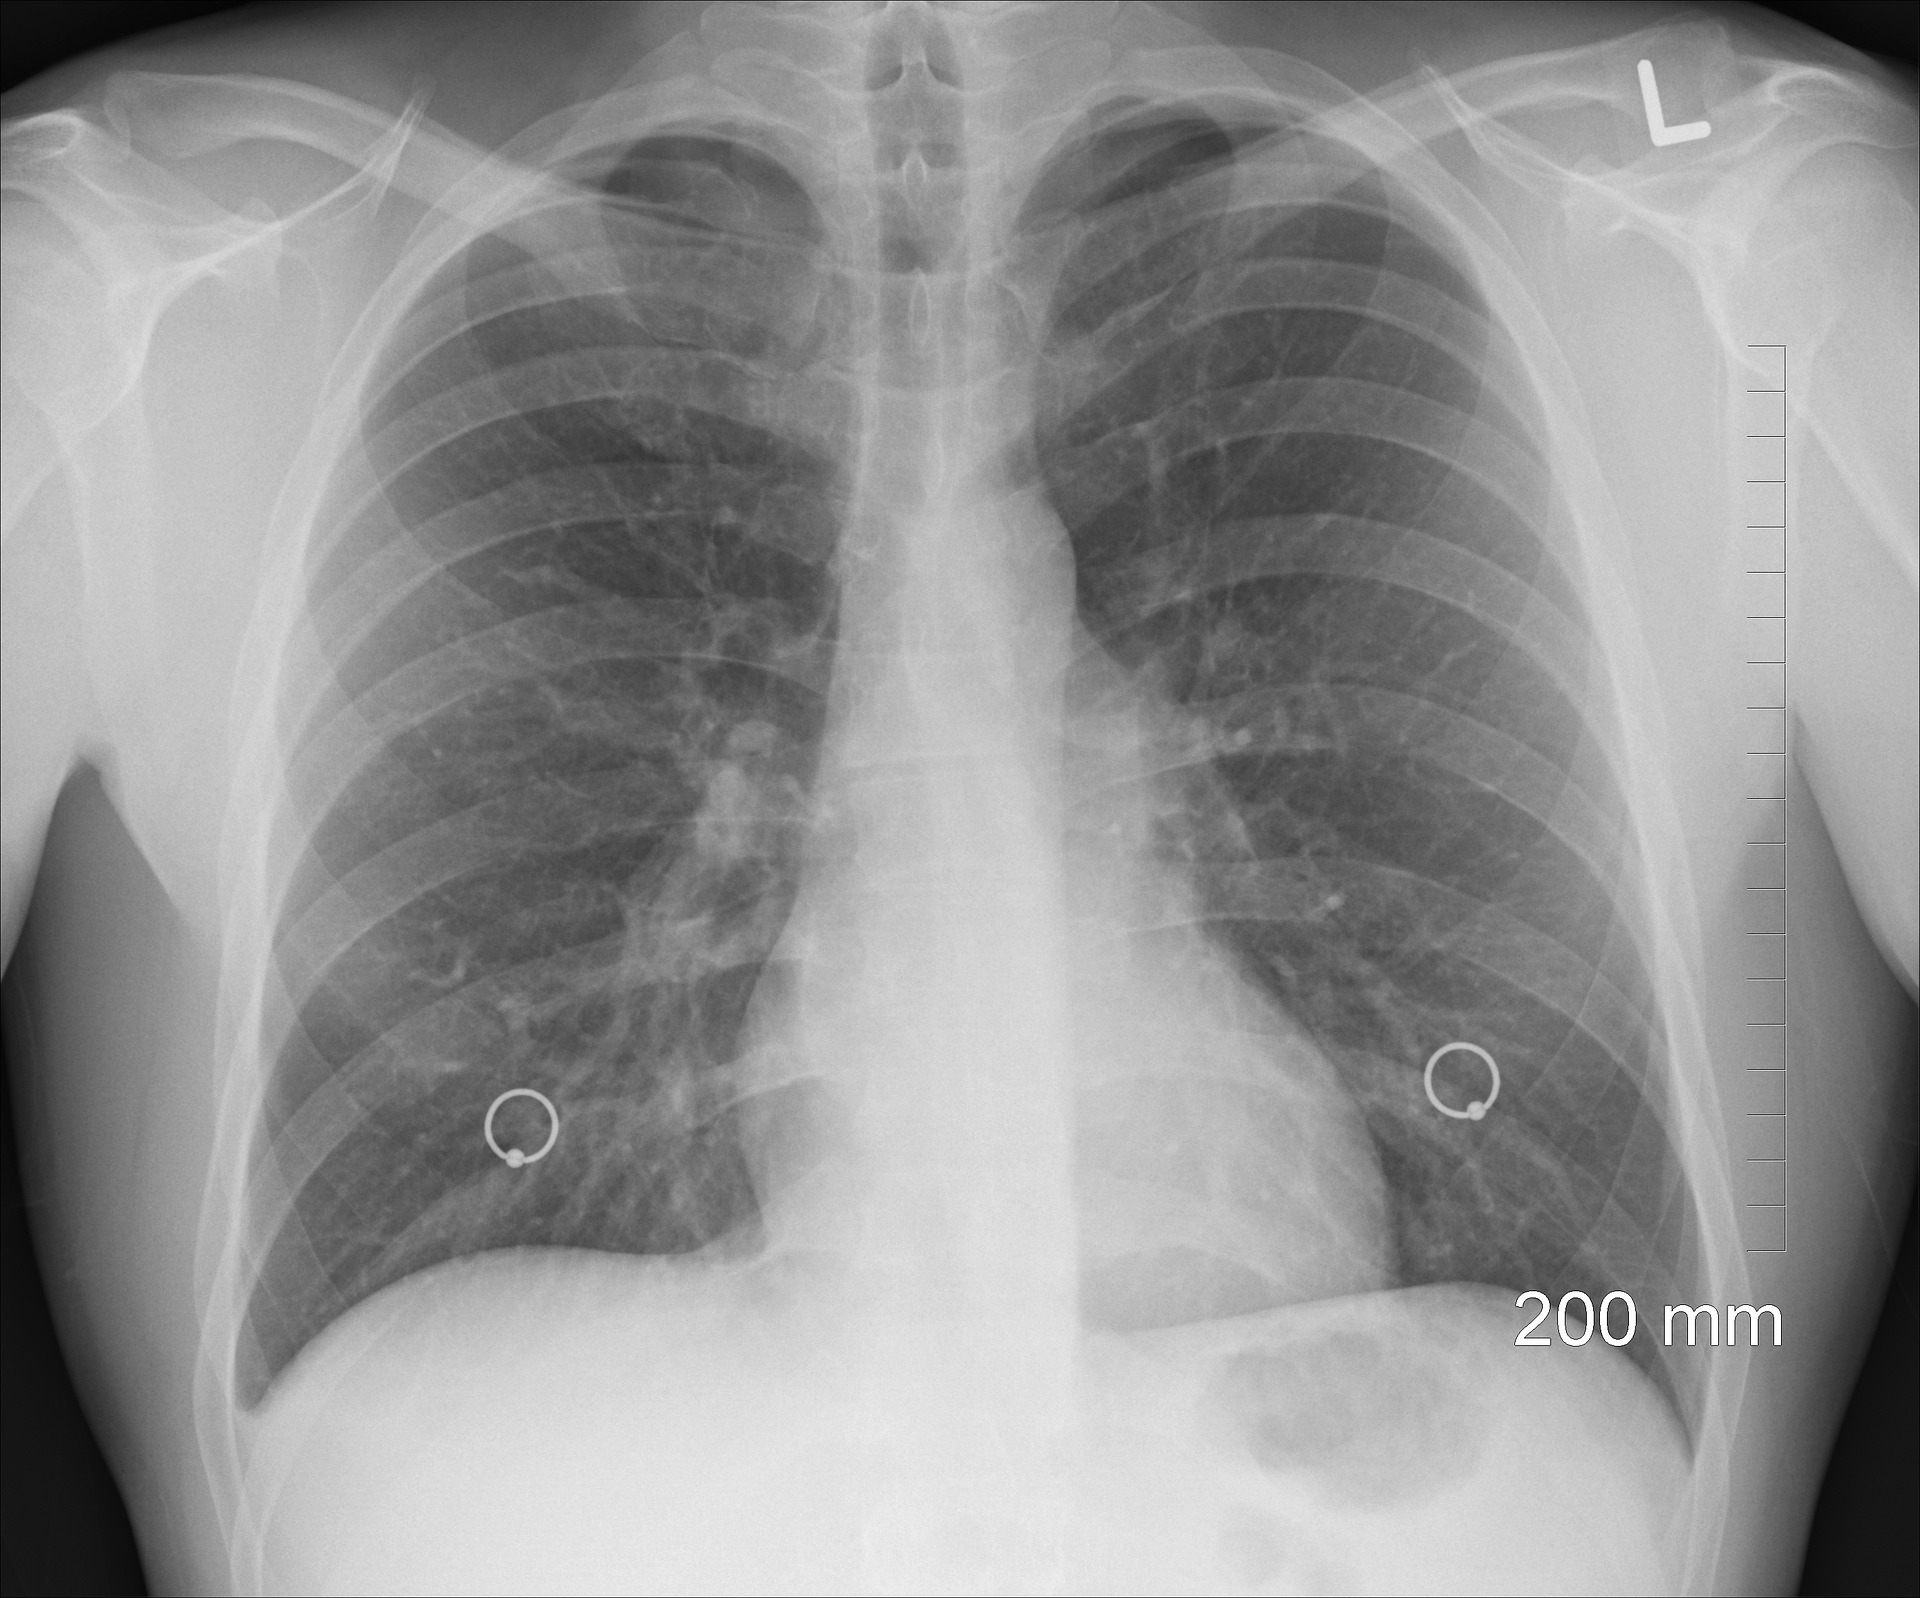

Welcome to the 2025-2026 spring term iteration of CS156b! As with last year, we'll be working with a dataset of radiograph images. Radiography is the most commonly used method of chest imaging, and has been a staple tool for diagnosis and screening of diseases. Automated anomaly detection in radiograph images would greatly assist medical professionals with correctly diagnosing these anomalies.